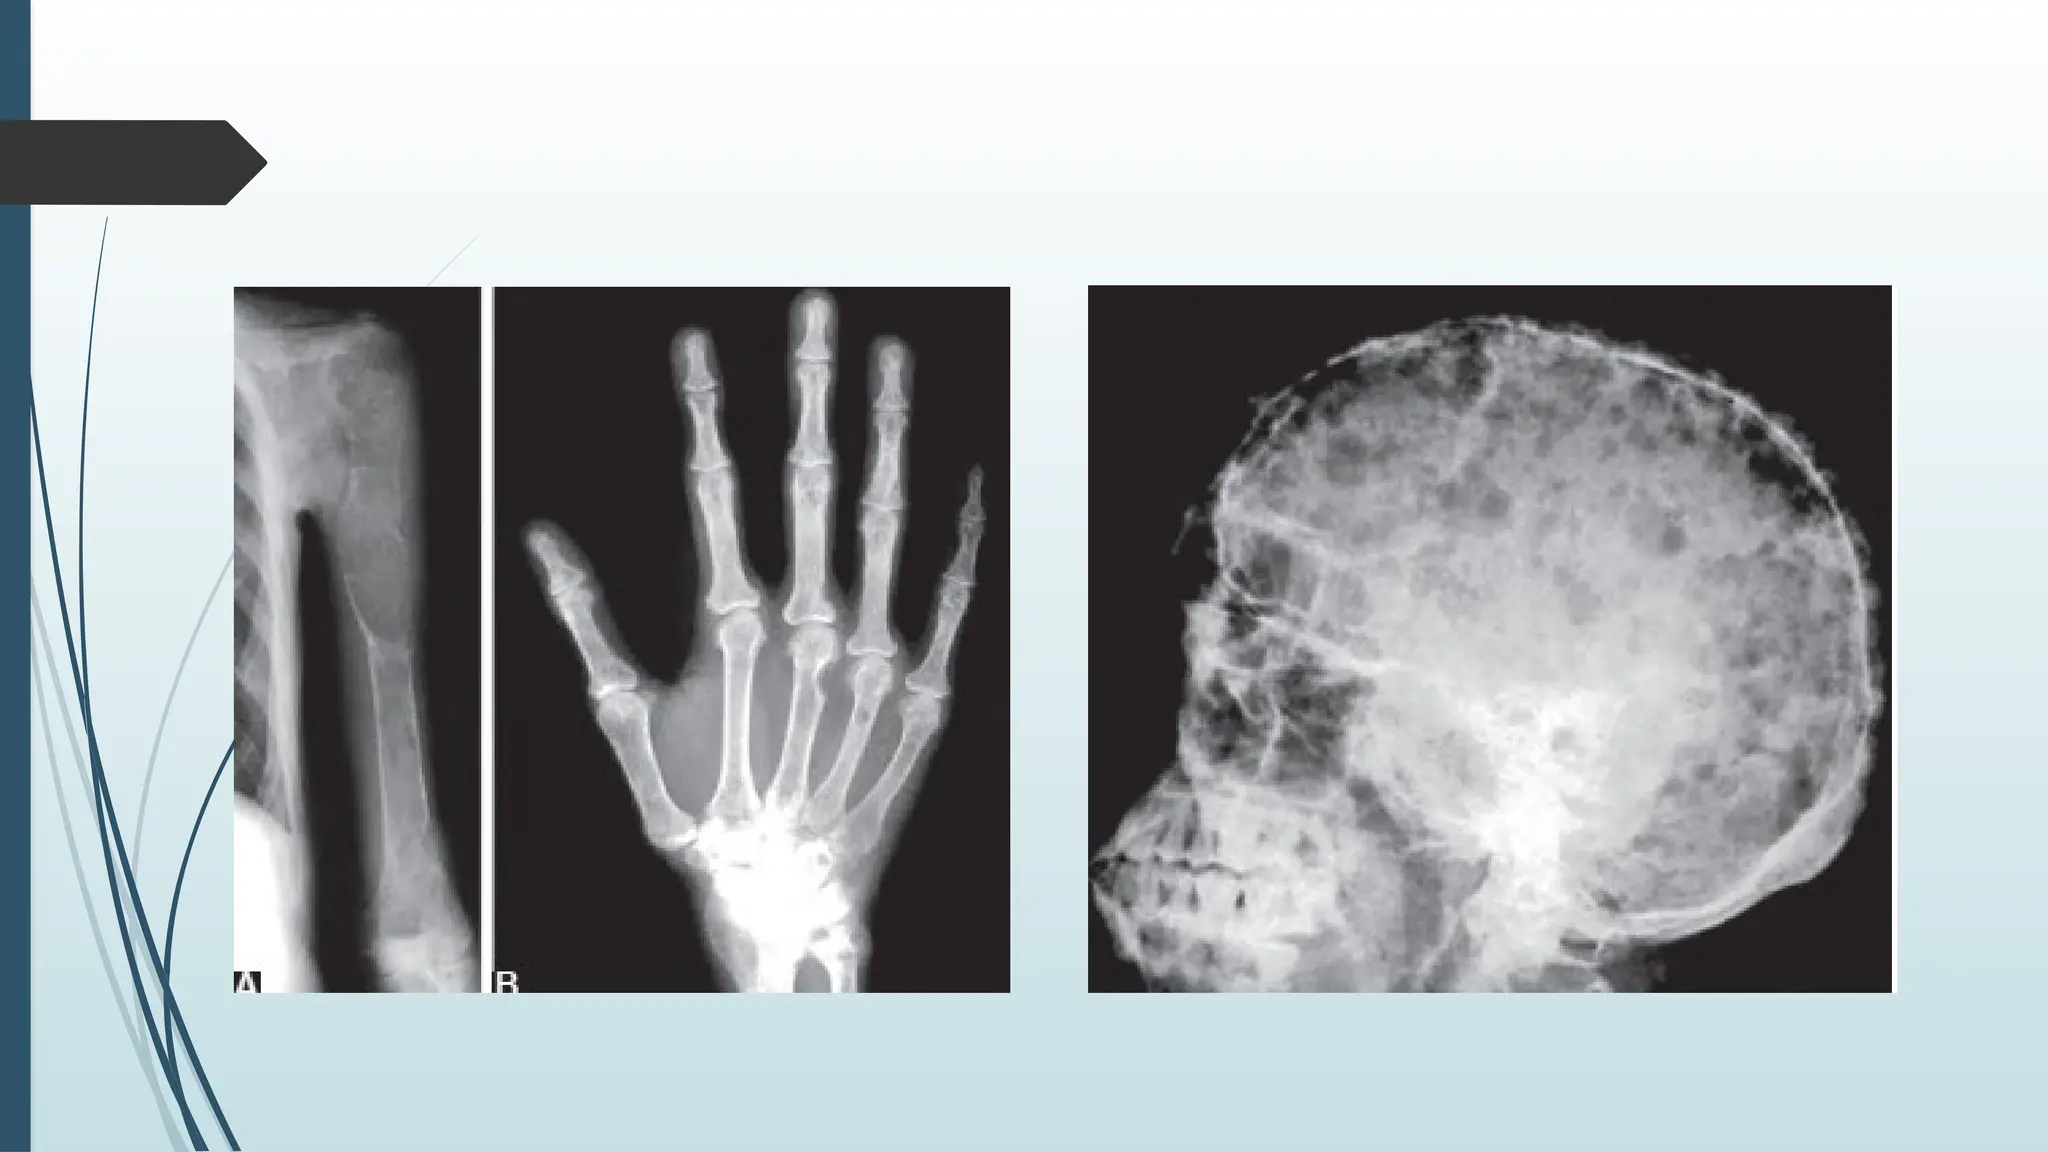

 X-ray skull shows salt and pepper appearance and brown

tumour

Bones :  Bone pain. Subperiosteal erosions on the radial aspect of the middle phalanges and clavicle.  Osteitis fibrosa cystica (Brown tumour ).

Investigations for HPT X-ray skull shows salt and pepper appearance and brown tumour  Ultrasound abdomen to find out problems in kidney, pancreas.  Ultrasound neck and CT/MRI scan neck and mediastinum.  Selective venous sampling for PTH is also very useful.  Thallium-Technetium scan shows hot spots which is diagnostic of parathyroid adenoma.  Technetium-99m labelled Sestamibi isotope scan is better and sensitive (80%)  single photon emission computerized tomography (SPECT)